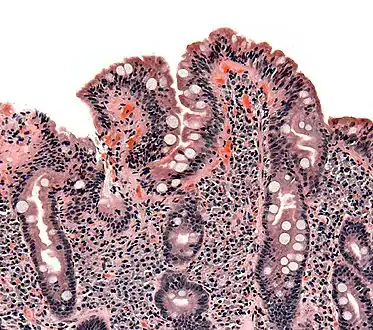

Biopsy of small bowel showing coeliac disease manifested by blunting of villi, crypt hypertrophy, and lymphocyte infiltration of crypts

The classic pathology changes of coeliac disease in the small bowel are categorised by the "Marsh classification":[99]

Marsh's classification, introduced in 1992, was subsequently modified in 1999 to six stages, where the previous stage 3 was split in three substages.[101] Further studies demonstrated that this system was not always reliable and that the changes observed in coeliac disease could be described in one of three stages:[18][102]

• A representing lymphocytic infiltration with normal villous appearance;

• B1 describing partial villous atrophy; and

• B2 describing complete villous atrophy.